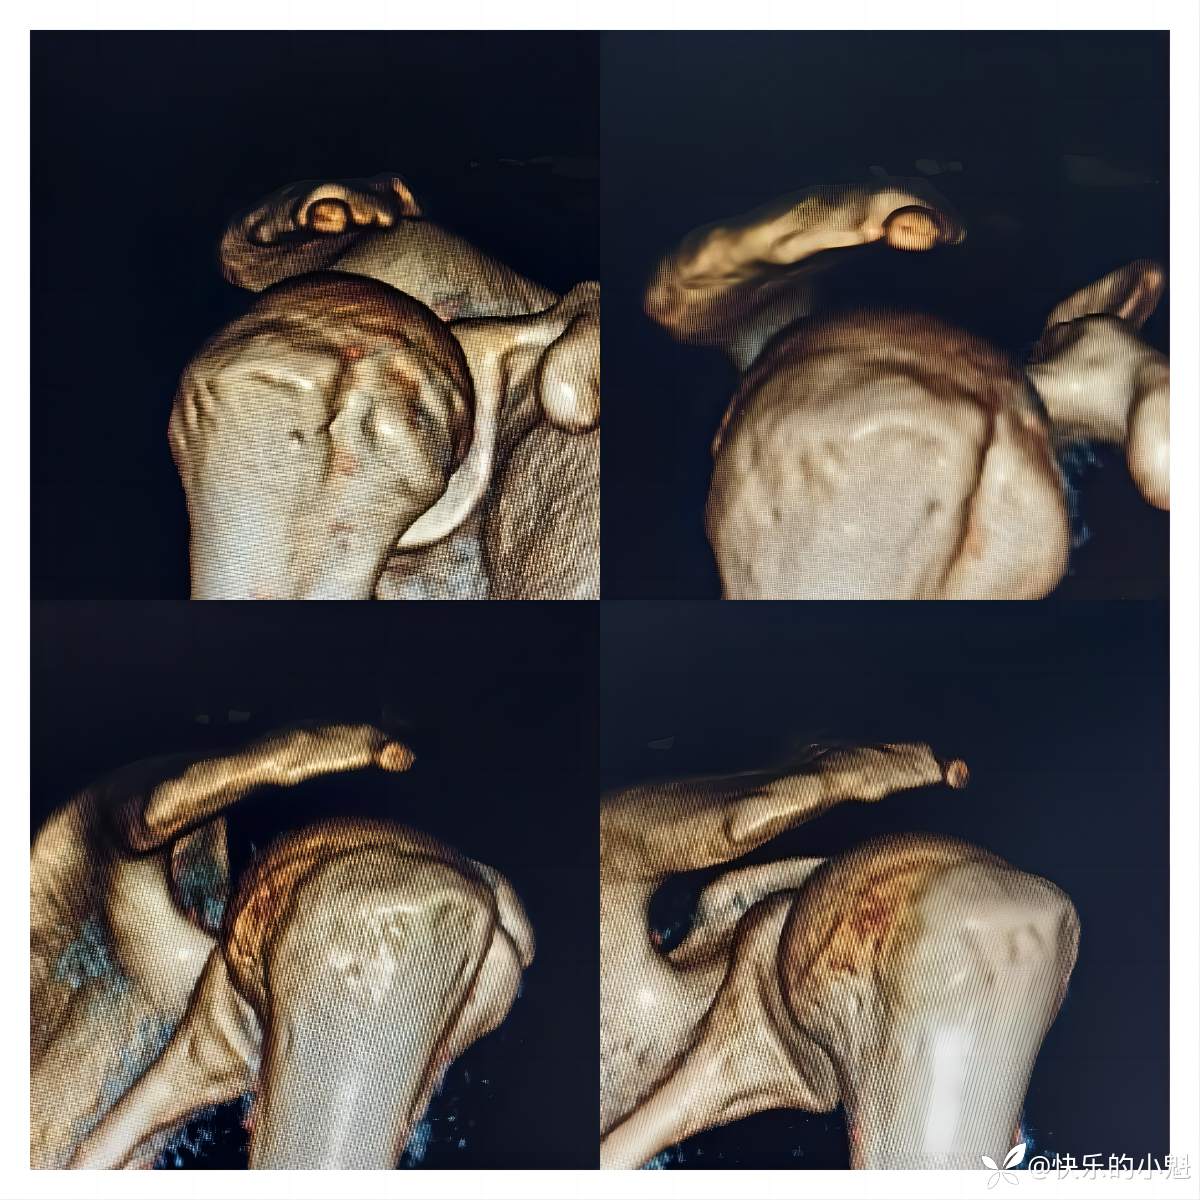

为此,进一步完善CT示:右侧肩峰增生,右侧肩峰前外侧缘小骨块(见下图)。